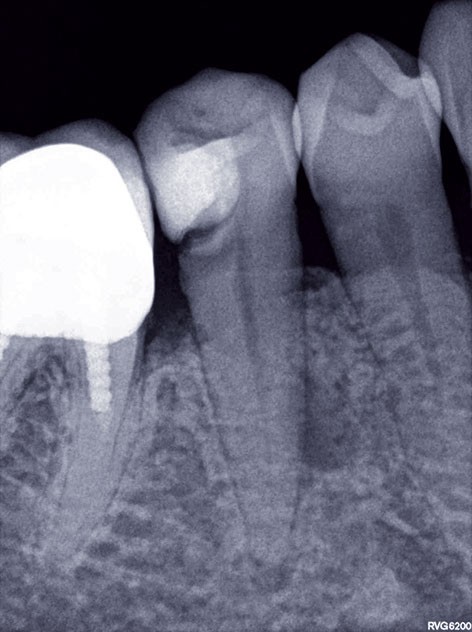

3, 4, 5. La restauration est déposée, les tissus carieux éliminés et la cavité d’accès aménagée avant la réalisation du traitement endodontique. La radiographie postopératoire permet de visualiser l’obturation du canal latéral en regard de la LIPOE.